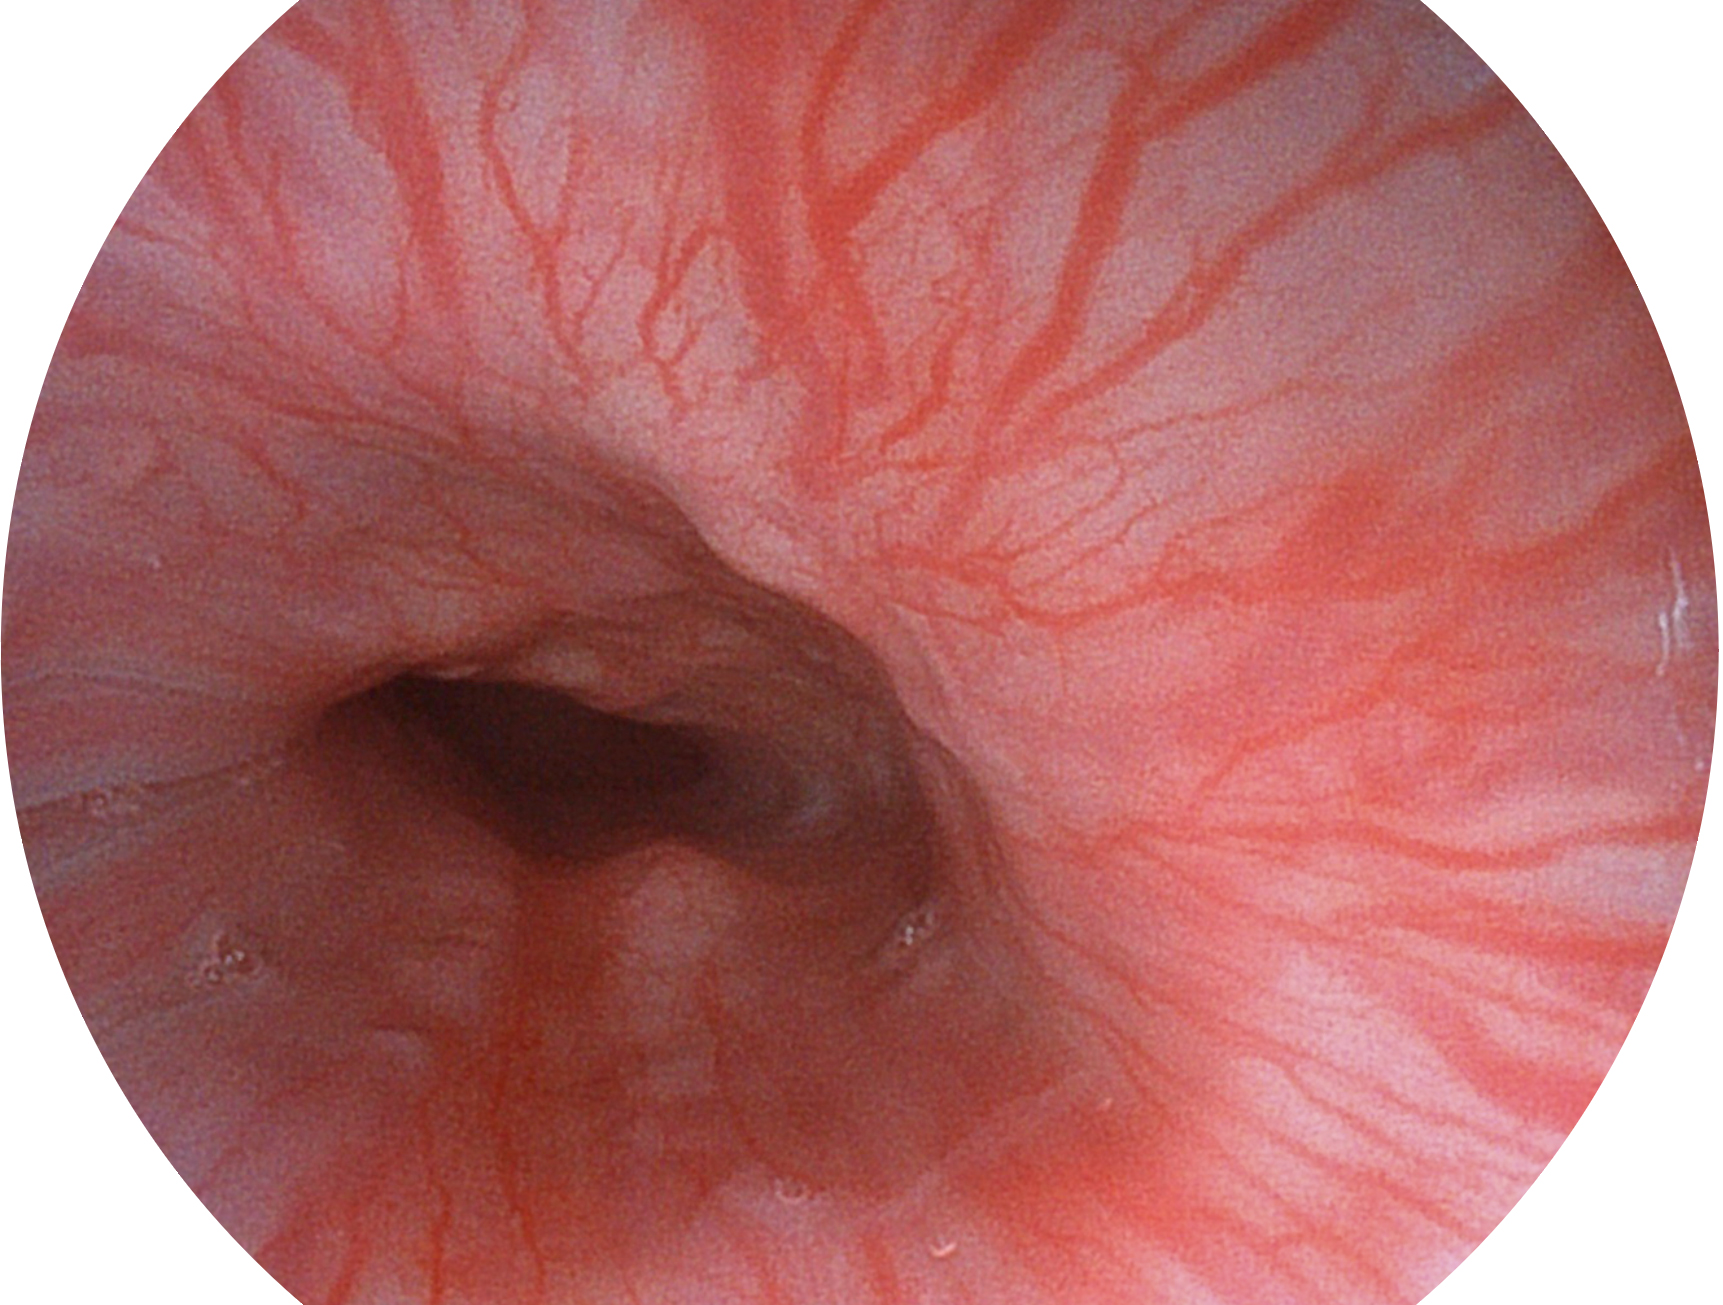

亚星官网新开发的内镜染色技术,主要是基于多波长LED 光源的开发,VLS-55Q 四波长LED 光源是由四个不同颜色的LED光按照相应照明模式所规定的特定发光比例进行合束后形成,合束后形成的照明光的光谱由红光、绿光、蓝光及蓝紫光这四个不同的波段范围构成。具有更高光谱自由度,通过光谱比例的控制,实现了聚谱成像技术,英文全称为“Spectral Focused Imaging, SFI”,缩写为“SFI”和光电复合染色成像技术,英文全称为“Versatile Intelligent Staining Technology, VIST”,缩写为“VIST”。